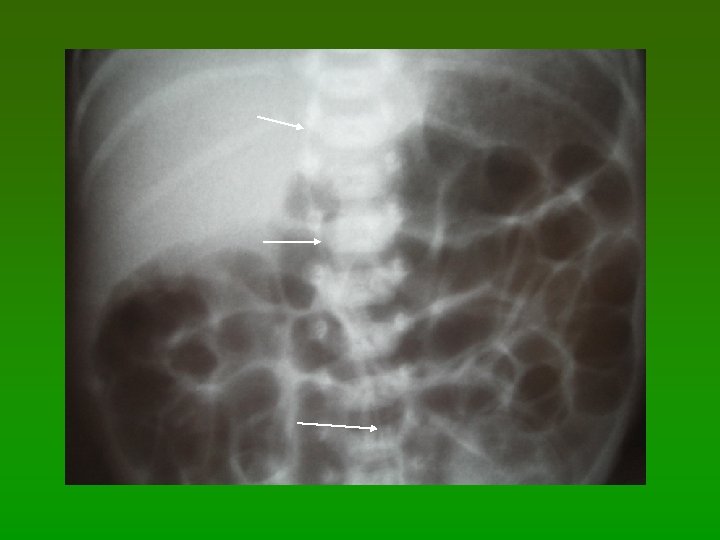

O cateter não deve ficar nesta posição!

Efusão Pericárdica e Tamponamento Cardíaco X Cateter Venoso Central § Apresentação Clínica: Edema de veia jugular ou ruborização Súbita necessidade de uso de drogas inotrópicas e de aporte ventilatório § Concentração média de efusão de glicose: 12, 5 gr § Associação com cirurgias torácicas § Localização da ponta do cateter visualizada no RX Intra cardíaco – Atrio direito Junção Atrio direito e veia cava Veia subclávia esquerda Ventrículo direito